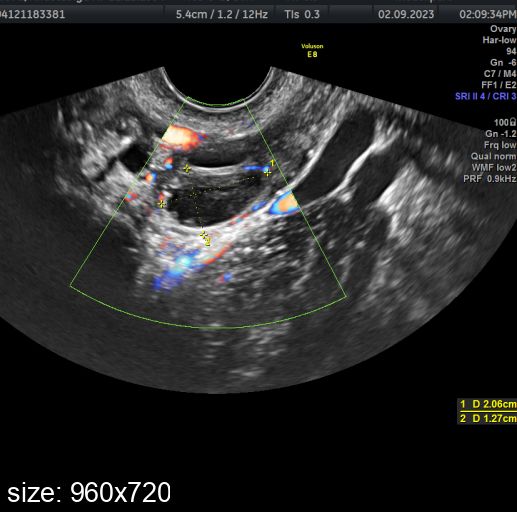

. 30 августа vs 2 сентября. Овуляция ориентировочно 1 сентября была

. 30 августа vs 2 сентября. Овуляция ориентировочно 1 сентября былаПрям вот хоть сейчас лопнуть может, так как 24 мм уже довольно приличный размер.